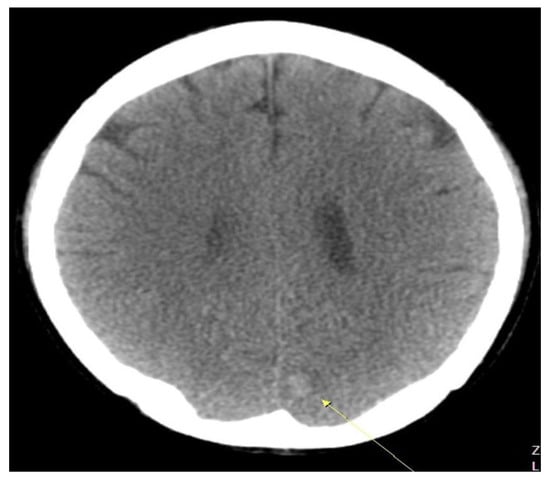

6.3. The Patient Was Treated with Anticoagulants—During Hospitalization, He Complained of Severe Headache without Neurological Symptoms, and a Brain CT Scan Showed Intracranial Hemorrhage